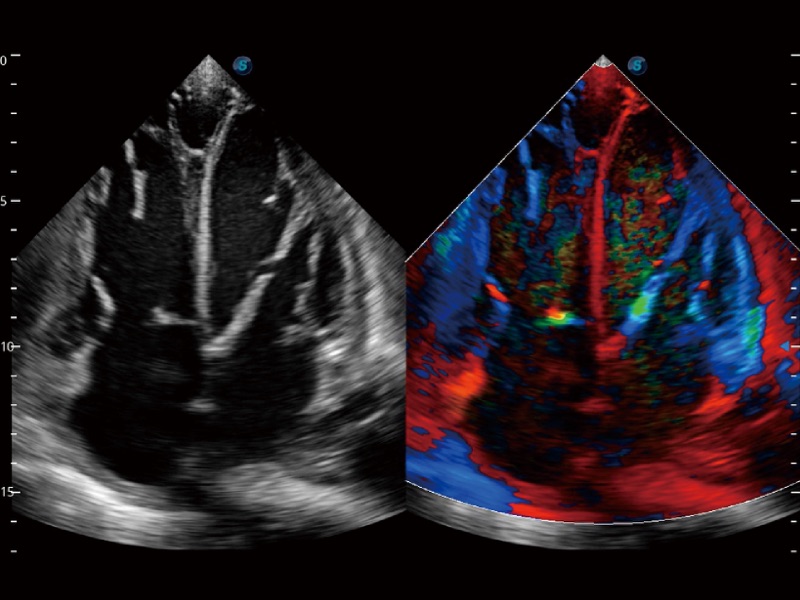

高分辨率血流成像技術(shù)提高了對低速血流信號(hào)的檢測能力。在提高空間分辨率的同時(shí),也克服了血流外溢現(xiàn)象,為用戶提供更加真實(shí)的血流動(dòng)力學(xué)信息。

心血管應(yīng)用

支持運(yùn)動(dòng)和藥物負(fù)荷協(xié)議、多心動(dòng)周期存儲(chǔ)選擇,為臨床觀察心肌負(fù)荷狀態(tài)下的室壁節(jié)段運(yùn)動(dòng)、評估心肌缺血狀態(tài)提供更多的解決方案。

通過心肌識(shí)別技術(shù)和二維斑點(diǎn)追蹤技術(shù)相結(jié)合,計(jì)算心肌各節(jié)段的應(yīng)變應(yīng)變率、速度、位移并以曲線圖顯示,實(shí)現(xiàn)整體或者局部心肌定量分析。同時(shí)可呈現(xiàn)牛眼圖直觀和準(zhǔn)確診斷心肌的運(yùn)動(dòng)情況。